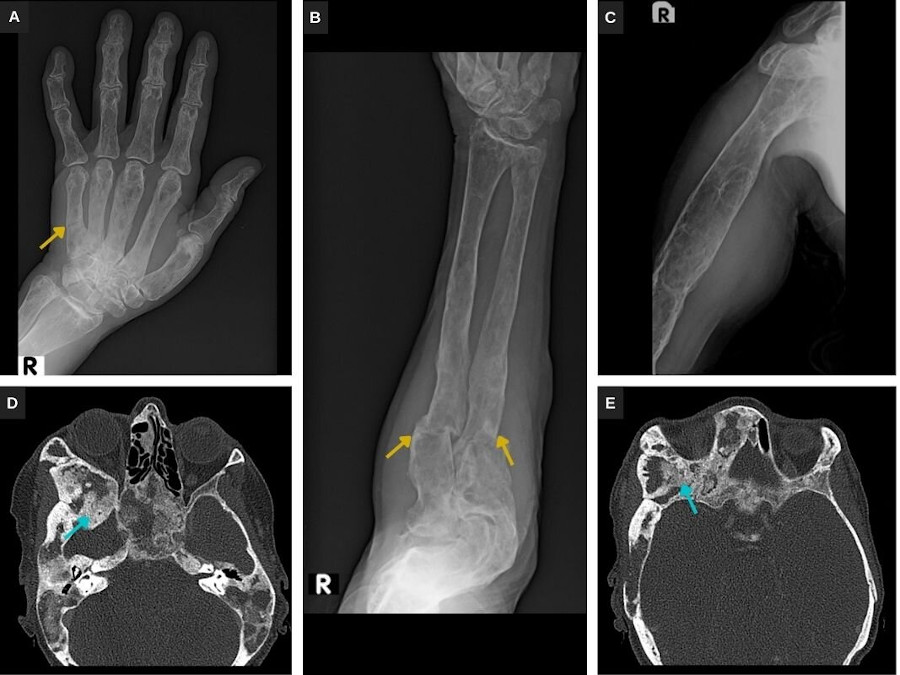

La displasia fibrosa asocia deformidad ósea y fracturas patológicas (Fig. 3). Los estudios radiológicos ponen de manifiesto el patrón en densidad mixta, con sectores en vidrio deslustrado, expansión y festoneado endostal (Fig. 3). En la RM las lesiones presentan señal heterogénea potenciada en T1 y T2, con sectores quísticos y captación heterogénea del contraste (Fig. 4).

Las técnicas de imagen son importantes para el diagnóstico y el seguimiento. Las radiografías y la TC de nuestro caso ponen de manifiesto los cambios óseos compatibles con displasia fibrosa: lesiones intramedulares, expansivas, de densidad mixta, con sectores en vidrio deslustrado característico de las lesiones fibrosas, que determinan festoneado endostal. En la RM presentan señal y captación heterogénea, predominantemente baja potenciada en T1 y de intermedia a alta en T2/STIR, con sectores quísticos. Si bien se evidencian deformidad ósea y fracturas patológicas como complicaciones de la displasia fibrosa, no se identifican signos sugestivos de transformación maligna.